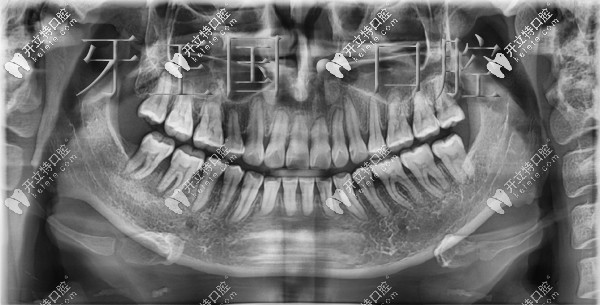

在西固區(qū)牙王國口腔做舌側(cè)矯正前后對(duì)比圖:

矯正前▼